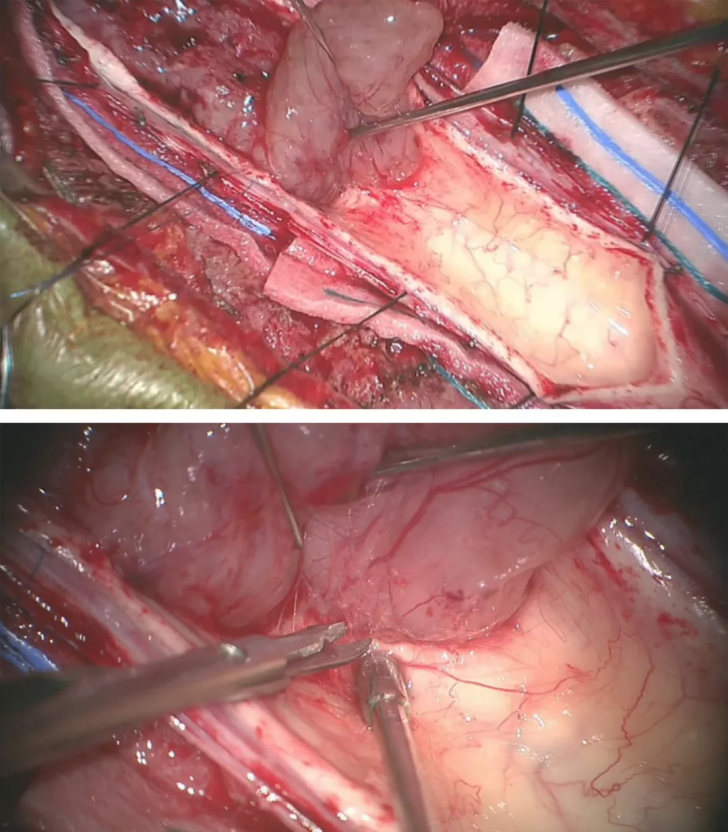

采用6-0 缝线牵开软脊膜来暴露肿瘤来减少术中反复牵拉脊髓造成损伤(A)。

肿瘤上较的空洞使得瘤体与脊髓界限清晰而易于分离(B)。

底图显示采用有角度的显微剥离子将肿瘤从脊髓剥离下来(C)。

采用娴熟的显微操作技术将瘤壁自菲薄的脊髓上剥离下来。由于肿瘤出血或空洞导致脊髓与肿瘤之间形成一个明显界面。大多数室管膜瘤和脊髓之间存在明显的肿瘤-脊髓界面。一般室管膜瘤的前方均有自脊髓前动脉发出的小动脉供血。在切除肿瘤时,这些肿瘤穿支血管要仔细分离、予以电凝后切断。盲目地牵拉会导致这些血管的撕裂,从而在止血过程中可能导致临近血管和脊髓的损伤。(下图)

术者在切除髓内肿瘤过程中遵循一些原则:在切除肿瘤过程中尽量牵拉肿瘤壁而非脊髓来暴露界面和视野。视野干净有利于保持分离界面清晰。先采用超声刀进行肿瘤减压以便于牵拉肿瘤过程中不造成脊髓损伤。术者不建议强行剥离室管膜瘤的囊壁,因为目前研究表明这些囊壁不含肿瘤细胞,但这一操作却会很有可能导致脊髓损伤。

3)在处理体大的血管母细胞瘤时,采用6-0 prolene缝线适当牵拉软脊膜以暴露瘤体,电凝供血动脉,较后完成瘤体分离后再切断引流静脉,较终切除肿瘤。